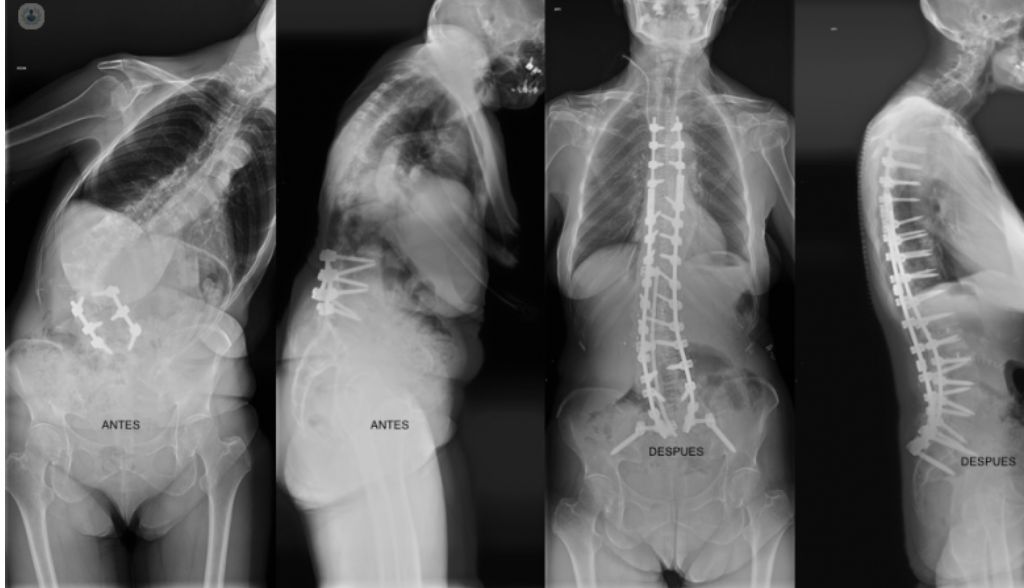

- Cifoescoliosis

Fotos y vídeos